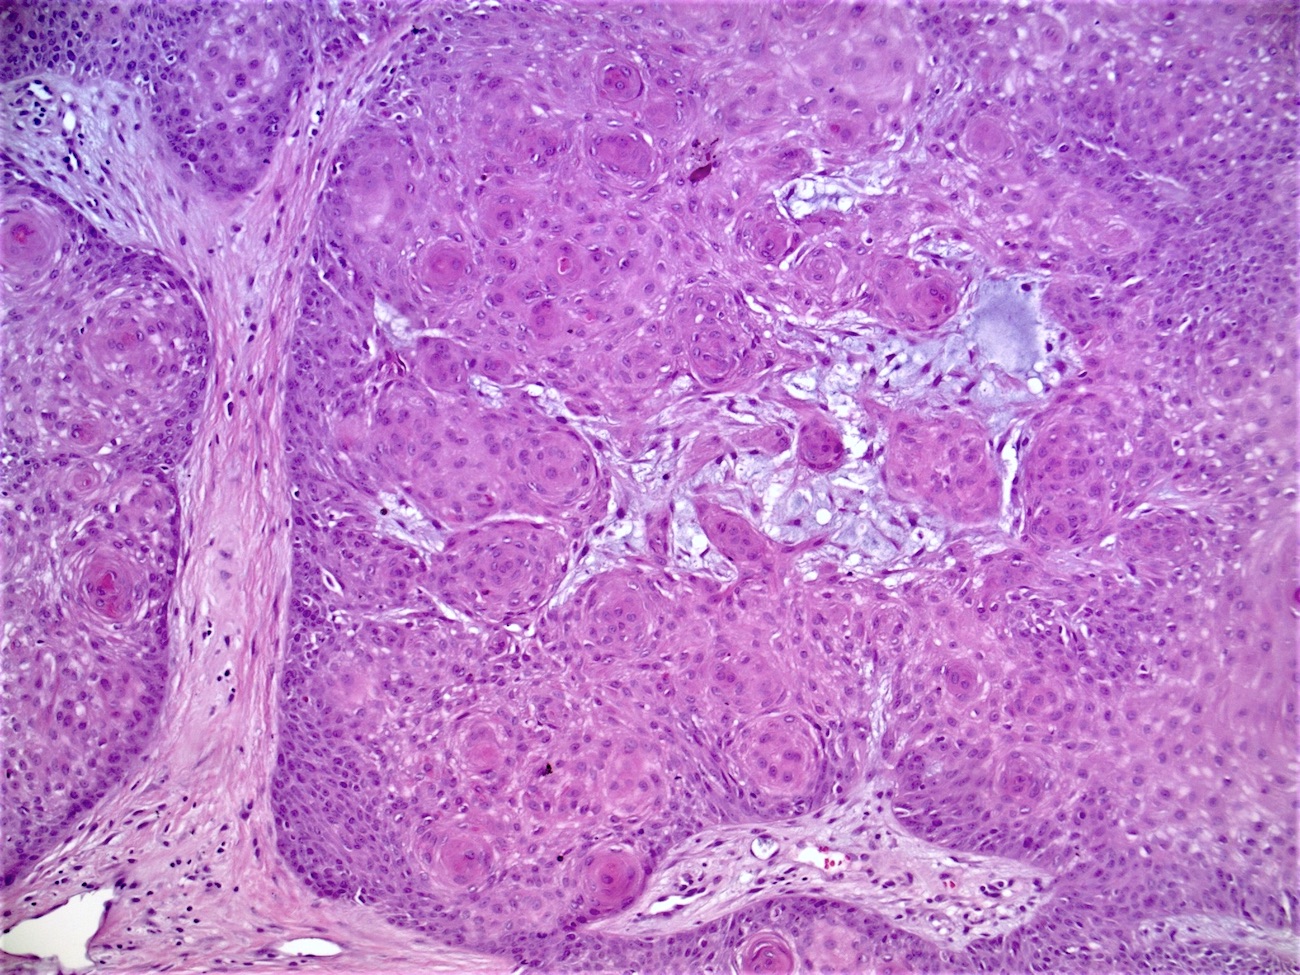

- Well circumscribed, endophytic tumor with large lobules or finger-like extensions that resemble expanded follicles

- Variable number of squamous eddies

- Cystic type: irregular clefts within tumor and formation of small cysts

Microscopic (histologic) images